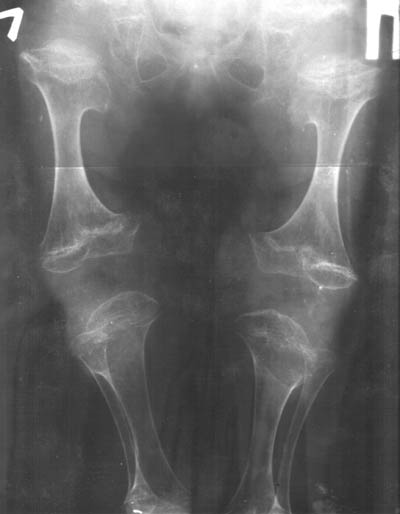

Девочка, 5 лет. Дз: спондилоэпиметафизарная дисплазия.Какое хирургическое лечение необходимо? Кто может принять на лечение?

A girl, 5 yrs old, living in Ukraine, needs an orthopaedic treatment due to subj.Can anybody tell, what kind of surgical corrections must be made now, and what are possible later.It is also important to know, what hospitals in Eastern Europe are the best to manage with that.Best regards,Andrew Yurtseniuk,orthopaedic surgeon,Chernivtsi, Ukraine

in spondyloepiphyseal dysplasia very rarely surgical corrections should be done (for example the epiphyseal dysplasia of the hip joints should not be treated like Perthes which looks similar than should be tretated conservatively).

In this special case the spine has to be treated and i would start with a brace (soft boston brace) to prevent further deformity of this kyphosis.

i would try to keep a good rom of all joints and buy time, i would discuss to perform an MRI investigation of the spine and the hips.